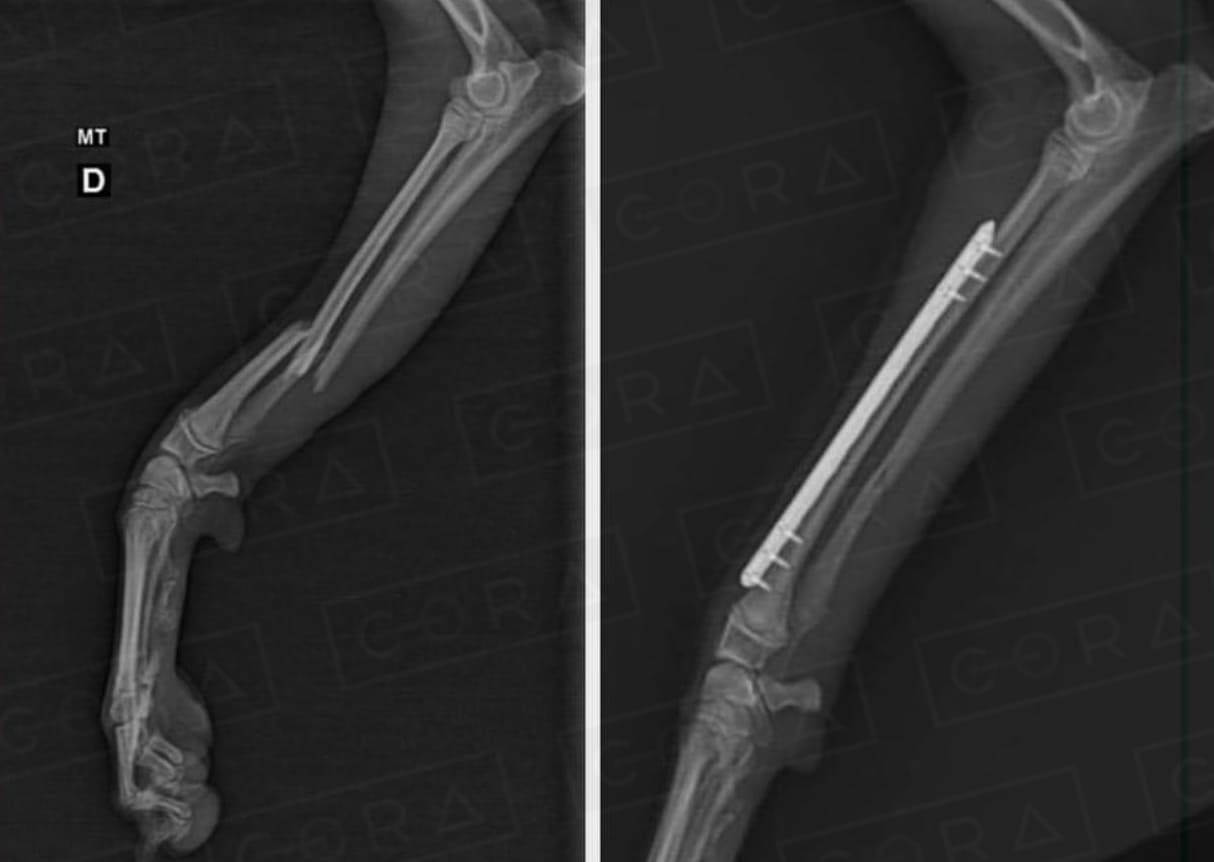

O diagnóstico é clínico e radiográfico. Algumas vezes são necessários demais exames complementares, como tomografia computadorizada.

Existem diversas técnicas de tratamento, desde as conservativas (com talas e bandagens) até as cirúrgicas, com o uso de implantes (placas, pinos, fios de aço, hastes bloqueadas, fixadores externos).